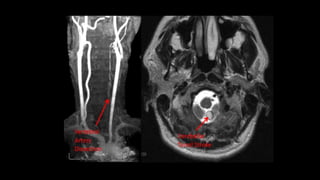

• #65 In this MR angiography of bilateral carotid system there is e/o short segment narrowing of Left ICA s/o left ICA stenosis

• #67 These are the sequences we take while characterizing plaque components . These are the things we look to characterize plaque